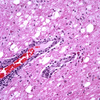

What is the term for phagocytosis of neurons by microglia/monocytes?

Neurophagia